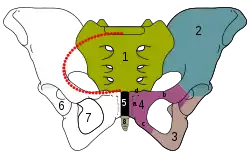

Hoftebenet, med tarmbenet farvet blåt. | |